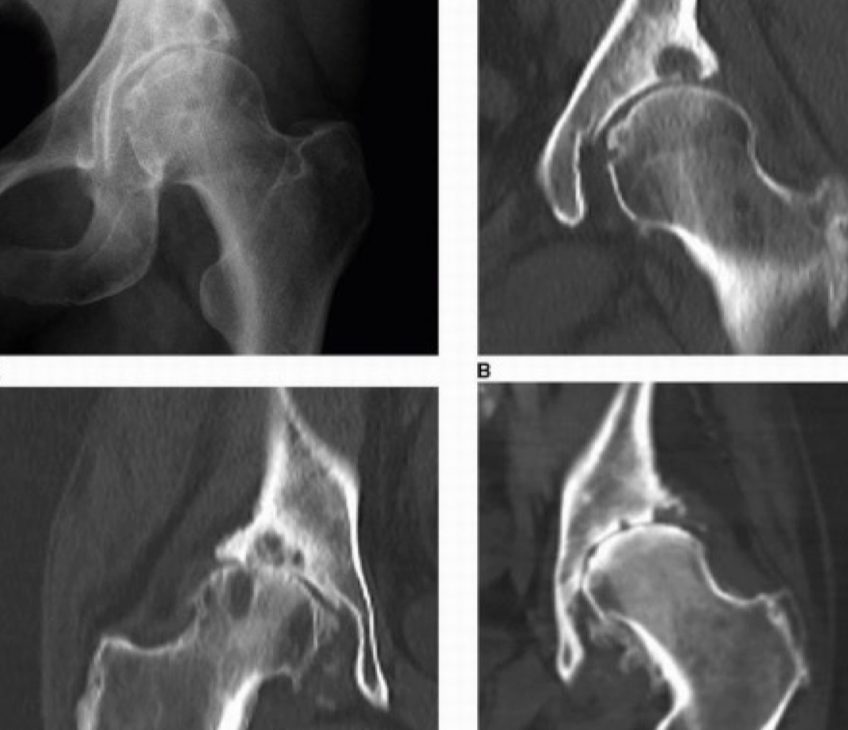

RX PZFAC

A

Ap y oblicua

Axial (Dunn)

6

Q

TC PZFAC

Permite mejor evalucación anatómica

Reconstrucción 3D